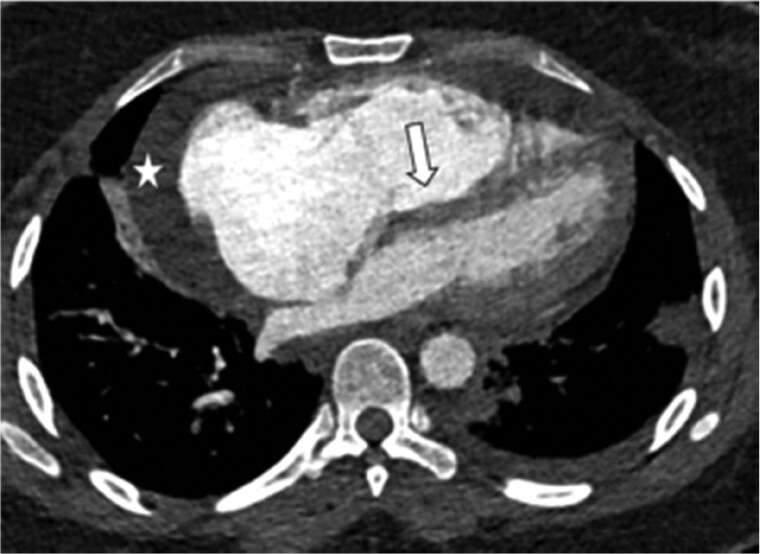

急性肺栓塞可以表现为一系列生理状态,从偶然发现到危及生命的右心衰。我们讨论了成像在准确和快速诊断中所起的关键作用。此外,影像学特征是评估表现严重程度的核心,允许适当的风险分层和护理升级。各种成像方式用于慢性血栓栓塞性肺动脉高压的管理的相对优势也进行了讨论。

Acute pulmonary emboli can manifest as a spectrum of physiological status ranging from an incidental finding to life threatening right heart failure. We discuss the crucial role imaging plays in the accurate and rapid diagnosis. In addition, imaging features are central in assessing the severity of the presentation allowing for appropriate risk stratification and escalation of care. The relative strengths of the various imaging modalities used in the management of chronic thromboembolic pulmonary hypertension are also discussed.